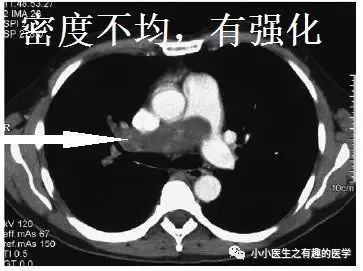

充盈缺损的地方,密度不均匀,并且有强化,血栓里面没有血管,一般不会强化,所以有可能是肿瘤。